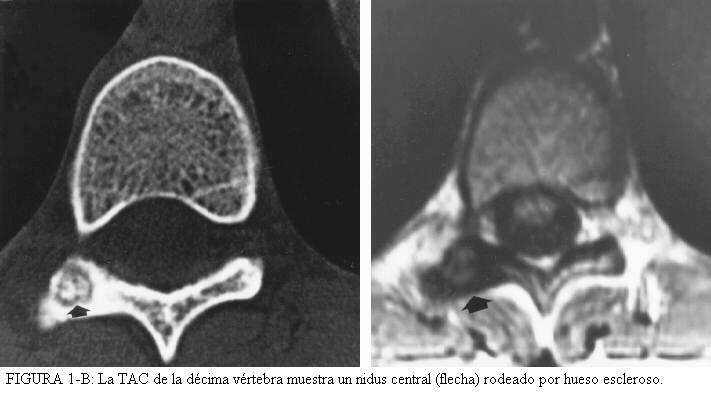

- osteoma osteoide de la columna: (figura 1-A y 1-B)

Hay que cuatro características diagnósticas que ofrece el osteoma osteoide. La lesión es redonda u ovoide y normalmente es menor de un centímetro de diámetro. El centro de la masa es homogéneamente densa, y hay una zona delgada, de uno a dos-milímetros radiolucente periférica. En un estudio, aproximadamente el 50% de 448 osteomas osteoide mostró todos estos rasgos. Los huesos normalmente involucrados eran el fémur (135 de 448, 30%), la tibia (121 de 448, 27 %), el húmero (cuarenta y cinco de 448, 10%), la columna (treinta y uno de 448, 7%), y el talus (dieciocho de 448, 4%). En los huesos largos, la lesión es normalmente intracortical; en la columna, involucra normalmente, los elementos posteriores ( Fig. 1A y Fig. 1B). El osteoma osteoide del talus normalmente se encuentra más en el cuello que en el cuerpo.

TAC:

El nidus se localiza mejor con  la CT, dicen los radiólogos, para el diagnóstico diferencial.

Los cortes deben ser de 1-2 mm para visualizar el nidus

Deben ajustarse las escenas de la ventana del escáner de CT para que la reacción densa alrededor de la lesión no disimule el pequeño nidus de densidad baja.

RM:

Generalmente la RM tiene un papel pequeño para el diagnóstico, porque el hueso tiene una señal baja.

A pesar de esto, puede usarse para confirmar el diagnóstico o ayudar a descartar otras lesiones.